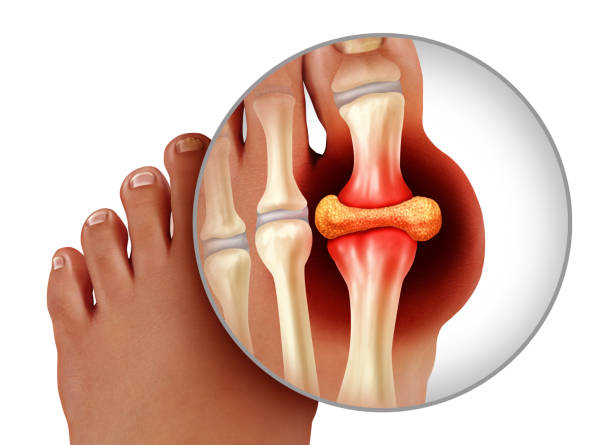

통풍은 요산이 너무 많아져서 혈액 내에 결정으로 축적됨으로써 발생하는 대사성 질환입니다. 요산은 일반적으로 신장을 통해 체내에서 배출되지만, 신장 기능이 저하되거나, 요산 생성이 과다한 경우에는 요산이 혈액 내에 축적되어 결정으로 형성됩니다. 이 결정이 관절 부위에 쌓이면 염증이 발생하여 통풍이 발생합니다. 따라서 상당히 고통스러운 통풍에 대해 보다 자세히 알아보기 위하여 원인, 증상, 치료방법 등을 자세히 알아보겠습니다.

염증

급성 통풍 발작은 관절 내부에서 염증이 발생합니다. 이는 염증을 일으키는 화학 물질이 적출물로 발적 주위에 축적되기 때문입니다. 염증은 일반적으로 통증, 붓기, 붉어짐 등을 초래할 수 있습니다.